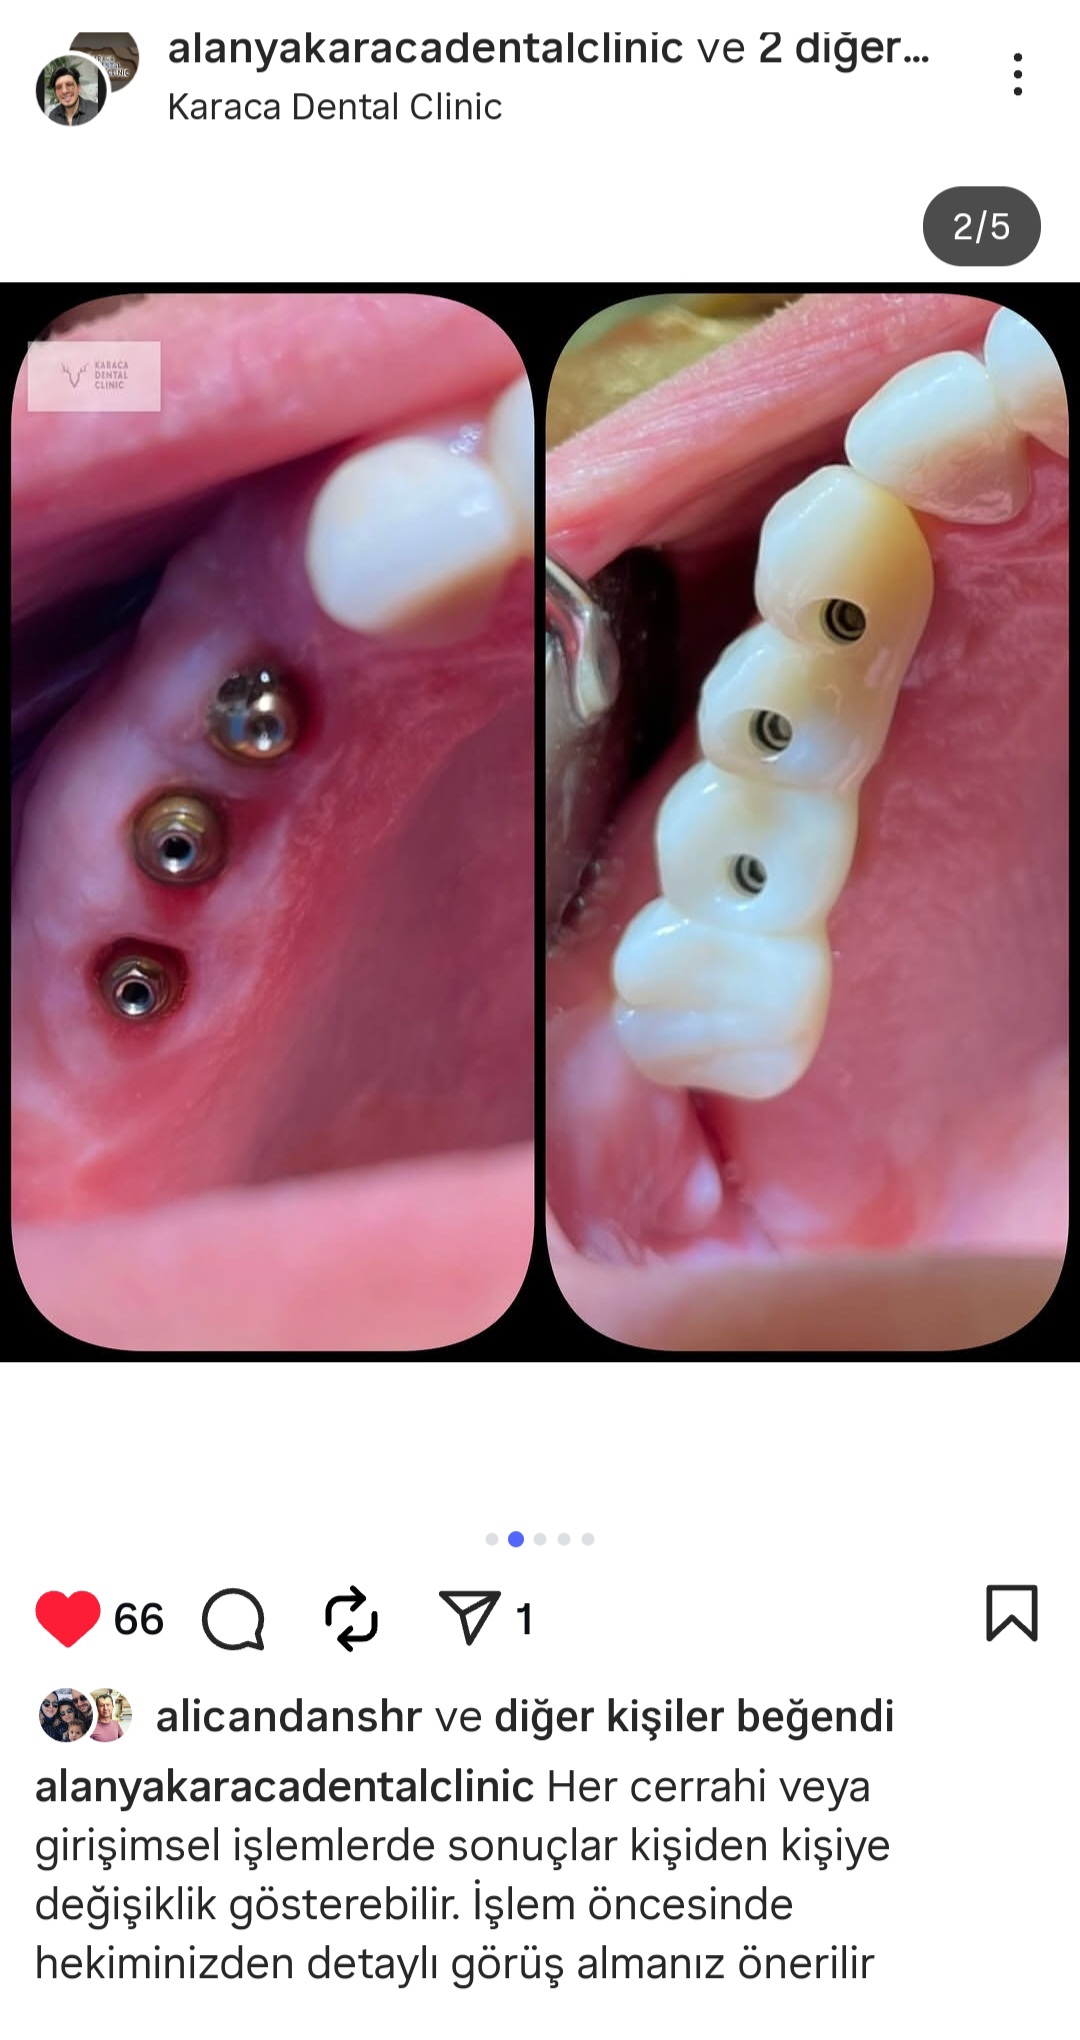

- Diş Dolgusu Kanal Tedavisi İmplant Tedavisi Çocuk Diş Hekimliği (Pedodonti) Lamina Kron Kaplama Zirkonyum Kron Kaplama Estetik Dolgu Estetik Gülüş Tasarımı Hollywood Gülüşü Diş Taşı Temizliği Air Flow Diş Temizleme Diş Beyazlatma Diş Çekimi Gece Plağı Dijital Diş Hekimliği 7/24 Diş Kliniği Hizmeti Acil Diş Kliniği Hizmeti Nöbetçi Diş Kliniği Hizmeti # HİZMETLERİMİZ #